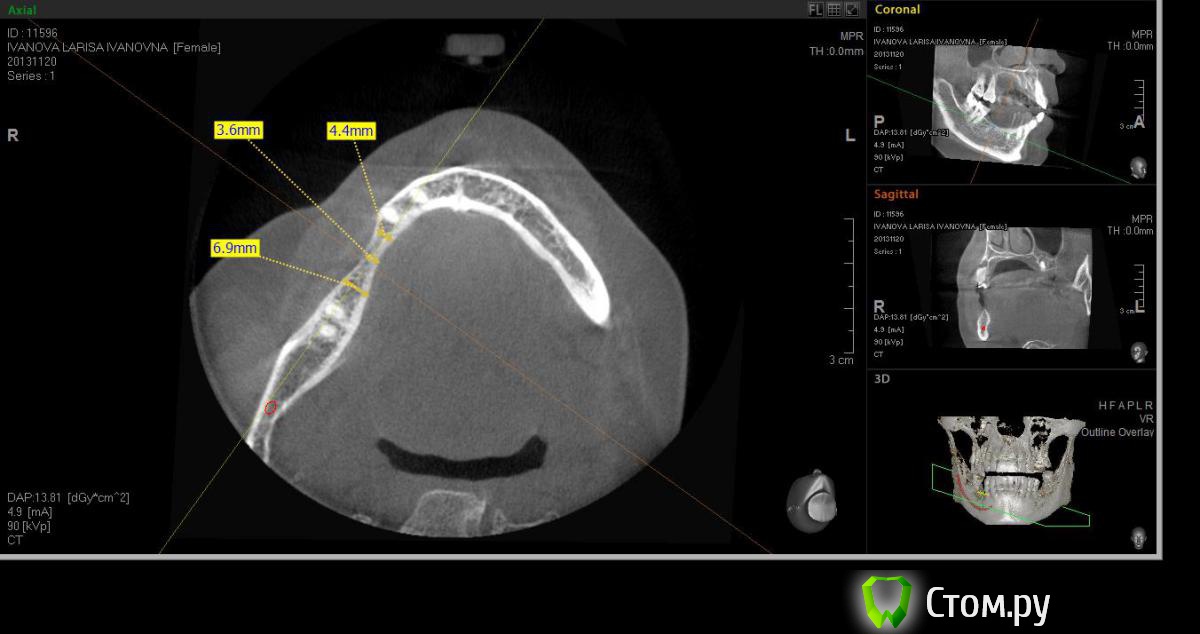

Neilrus Опубликовано 2 марта, 2014 Поделиться Опубликовано 2 марта, 2014 (изменено) Здравствуйте, коллеги, уделите 6 минут новичку…у меня тут проблема, она абсолютно не проблема для того, кто хоть пару раз делал расщепление гребня,а я вот только курсы закончил и у меня планируется через 7 дней операция. Вроде все понял, но пока стремаюсь.Посморите снимки, пожалуйста, а я напишу тот протокол, который хочу применить, как на курсах понял, поправьте, если что не так )) Спросил бы у лектора, но ведь так всегда, да?)Планирую иплантаты по месту 45,46 зубов.Гребень узкий в обл 45 з и близко нч нерв, как раз поднимается к ментальному отвертстию. С этим и связан страх. Никаких транспозиций делать пока не готов. В арсенале нет пьезотома пока, вот пару таких операций сделаю и куплю.Планирую поставить 4,2*8 для 45 зуба и 4,2*11,5 для 46 зуба (Мis Seven) . Соединю коронки, т.к. премоляр коротковат. Итак, план по захвату таков:1)Разрез чуть язычнее середины гребня, откидываем слиз-надк лоскут с аккуратностью в области менталиса.2)По центру гребня делаем горизонтальный распил сепарационным диском диаметром 7 не доходя до зубов по 3 мм. Глубина распила получается 3,3. Потом беру диск 10 и глубина уже 4,8.3)Мелким 7мм диском делаю дистально вертикальный распил на глубину 3,3 длиной с длину имплантата моляра 11,5, а медиально тем же диском на длину 4-5 мм, ниже страшно, боюсь нерв задеть. На верхушке гребня соединяем распилы (черные линии на моем рисунке). Делаем бором твердосплавным шаром компактостеотомию в преполагаемом месте перелома.4)Берем долото и вставляем в горизонтальный разрез и постукиваниями молоточка продвигаем его на глубину до 8мм по всей длине разреза (длина миниального импланта). Чуть покачивая из стороны в сторону, при этом убирая закругления от диска внутри горизонтального распила. (На рисунке, который сам нарисовал – это красная зона).5)Немного раздвинув края в месте предполагаемых имплантатов пилотом 2мм прохожу на глубину имплантатов. Проверяем параллельность.6)Загоняю по очереди мисовские компрессионные винты на глубину имплантатов до диаметра третьего винта 2,4- 3,7 (т.к. импланты 4,2)7)Теперь они вроде как должны быть нормально раздвинуты ( здесь я не понял, нужно проходить фрезами из хир набора или так хорошо войдут) Может финишной фрезой пройти хотя бы на всю глубину имплантатов? Подскажите, пожалуйста.8)Дальше заполняю пустоты MP3, фиксирую пинами MCT 2.75 мембрану evolution толстую на 2 мм ниже коспактостеотомии, перекидываю на язычную сторону под надкостницу краешек запихиваю.9)Мобилизую лоскут, ушиваю все наглухо и надеюсь на лучшее. ВОПРОСЫ:1)не коротковат ли имплант 4,2*8, но ведь я соединю их? Можно немного наклонить его медиально, выход шахты оставить там же, но апикальную часть ближе к моляру, тогда длина 10 выйдет, но там и так не получается соостно с зубами имплант размстить, а тут его и такая ангуляция, не хорошо, я думаю.2)Отслойка лоскута медиально- правильно я написал или порвется тогда и лучше рассечь связку на 44 и медиально вниз.3)Фрезы хирургические нужно использовать при нормальном раздвигании краев гребня? Кстати, нормально-это сколько для диаметра имплантата 4,24)Язычно нужно как-то дополнительно фиксировать мембрану?5)MP3 мешать с аутокостью и кровью из ловушки?6)Как лоскут мобилизовать медиально рядом с ментальным нервом? Пластика зкпд будет одновременно с открытием.Спасибо вам за ваше время ) Изменено 8 мая, 2014 пользователем Bier Ссылка на комментарий